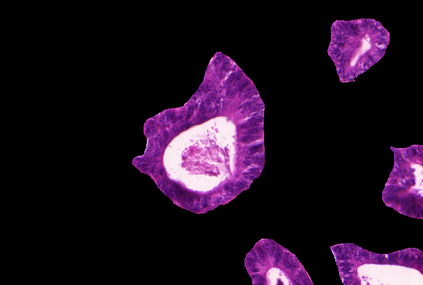

Weakly-supervised learning (WSL) has recently triggered substantial interest as it mitigates the lack of pixel-wise annotations. Given global image labels, WSL methods yield pixel-level predictions (segmentations), which enable to interpret class predictions. Despite their recent success, mostly with natural images, such methods can face important challenges when the foreground and background regions have similar visual cues, yielding high false-positive rates in segmentations, as is the case in challenging histology images. WSL training is commonly driven by standard classification losses, which implicitly maximize model confidence, and locate the discriminative regions linked to classification decisions. Therefore, they lack mechanisms for modeling explicitly non-discriminative regions and reducing false-positive rates. We propose novel regularization terms, which enable the model to seek both non-discriminative and discriminative regions, while discouraging unbalanced segmentations. We introduce high uncertainty as a criterion to localize non-discriminative regions that do not affect classifier decision, and describe it with original Kullback-Leibler (KL) divergence losses evaluating the deviation of posterior predictions from the uniform distribution. Our KL terms encourage high uncertainty of the model when the latter inputs the latent non-discriminative regions. Our loss integrates: (i) a cross-entropy seeking a foreground, where model confidence about class prediction is high; (ii) a KL regularizer seeking a background, where model uncertainty is high; and (iii) log-barrier terms discouraging unbalanced segmentations. Comprehensive experiments and ablation studies over the public GlaS colon cancer data and a Camelyon16 patch-based benchmark for breast cancer show substantial improvements over state-of-the-art WSL methods, and confirm the effect of our new regularizers.